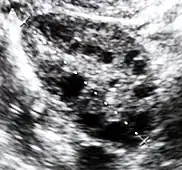

| Diagnostic method | Blood tests, ultrasound[1][4] |

The cause in about 70% of cases is polycystic ovary syndrome (PCOS).[1] Other causes include adrenal hyperplasia, Cushing's disease, certain types of cancers, and certain medications.[1][3][4] Diagnosis often involves blood tests for testosterone, 17-hydroxyprogesterone, and prolactin as well as a pelvic ultrasound.[1][4]

Polycystic ovary syndrome (PCOS) is an endocrine disorder characterized by an excess of androgens produced by the ovaries. It is estimated that approximately 90 percent of women with PCOS demonstrate hypersecretion of these hormones.[13] A concrete cause for this condition is currently unknown. Speculations include genetic predisposition, although the gene or genes in particular have yet to be identified.[14] Evidence suggests that the condition may have a hereditary basis. Other possible causes include the effects from an increase in insulin production. Insulin itself has been observed capable of inducing excess testosterone levels in the ovaries.[15]

Elevated insulin concentration in the body leads to lower production of sex hormone binding globulin (SHBG), a regulatory glycoprotein that suppresses the function of androgens.[16] High blood levels of insulin also work in conjunction with ovarian sensitivity to insulin to cause hyperandrogenemia, the primary symptom of PCOS. Obese individuals may be more biologically inclined to display PCOS due to markedly higher amounts of insulin in their bodies. This hormonal imbalance can lead to chronic anovulation, in which the ovaries experience difficulty releasing mature eggs. These cases of ovulatory dysfunction are linked to infertility and to menstrual disturbances.[13][17]